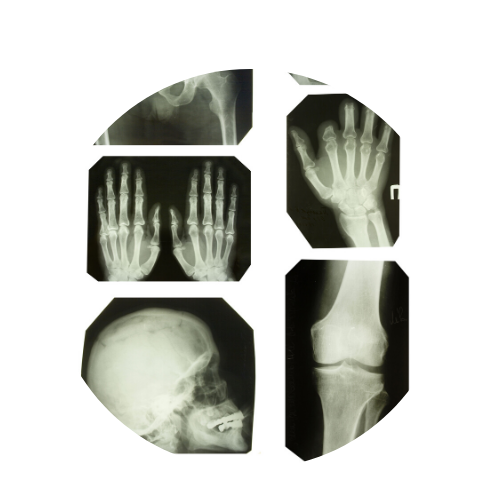

Fractures / Splinting

Many basic fractures and broken bones can easily be diagnosed and treated at an urgent care facility. We can also treat sprains, strains, and tendon injuries. At both ERgent Med locations, we offer X-rays, splinting, and if necessary, we can arrange for a visit with an orthopedic specialist or physical therapy right away for further treatment.

XRays

ERgent Med can perform X-Rays with speedy results, including chest X-rays, orthopedic X-rays, neck and back x-rays. We can also send you with a copy of your results and images for your specialist to review if necessary.